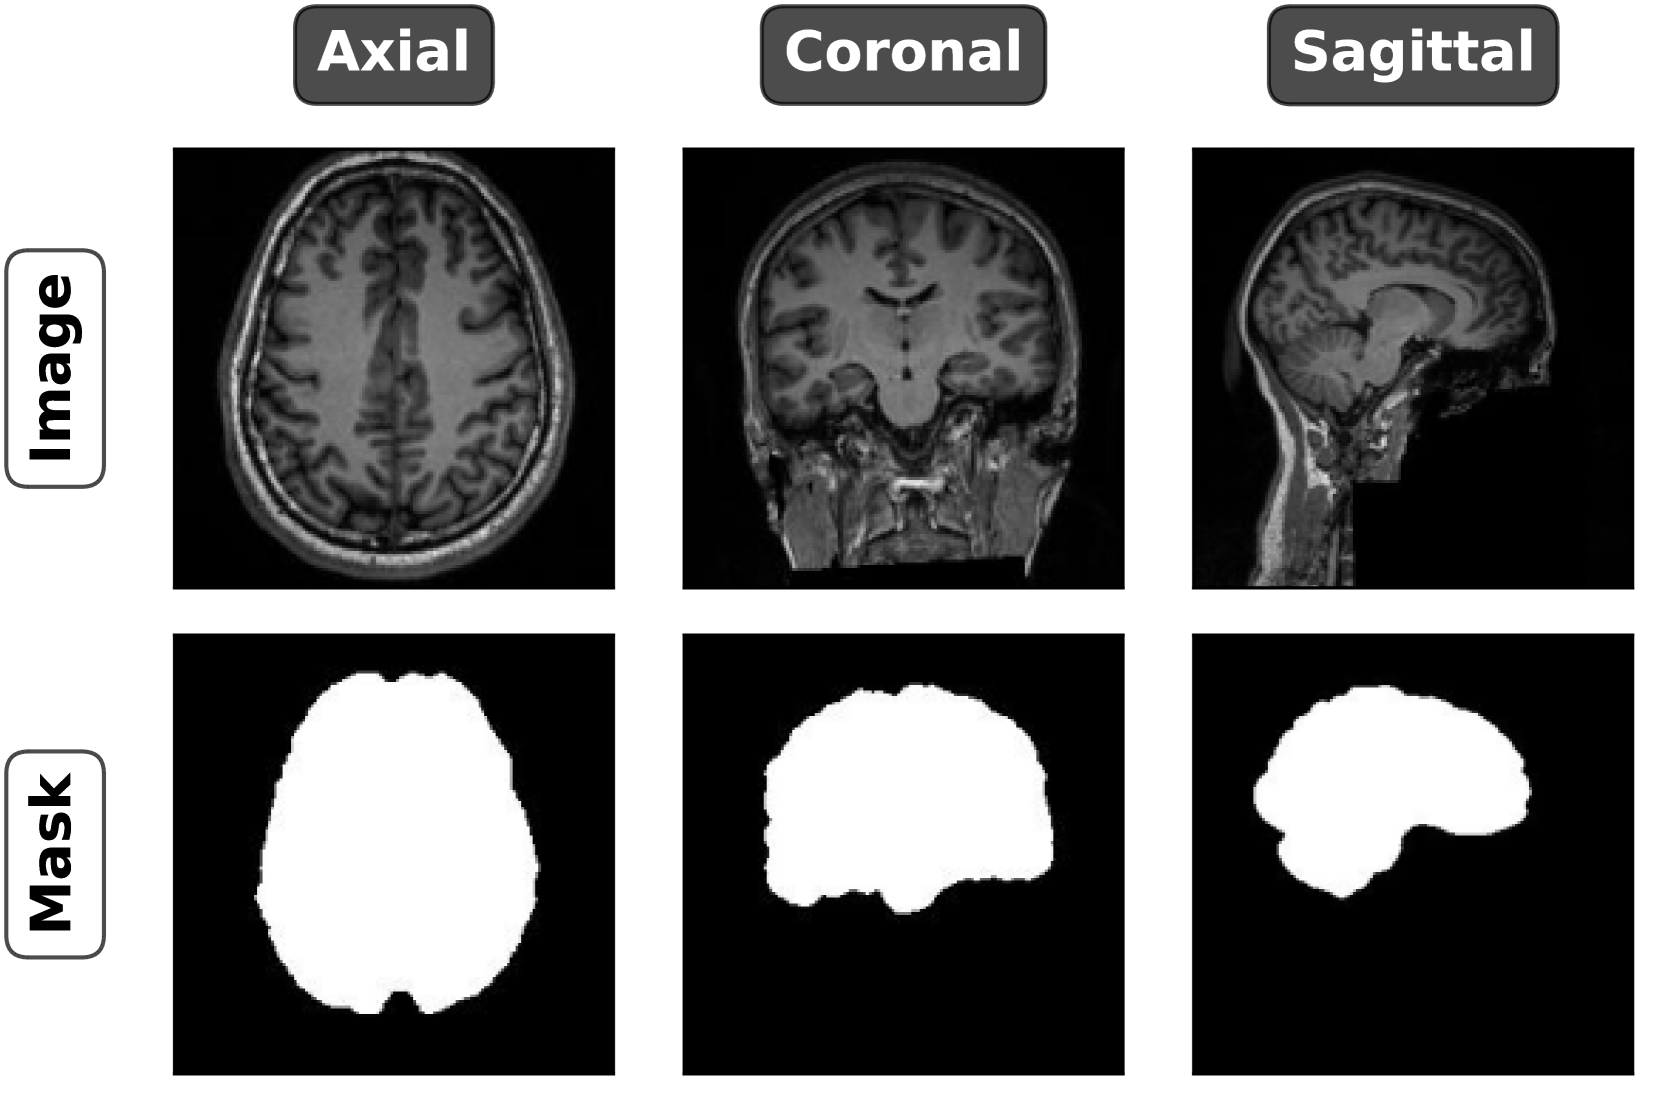

Figure 1: Subfigure (a) illustrates the 3D MRI volume in a three-dimensional coordinate system, where the brain is represented as a collection of voxels, forming the full anatomical structure. Subfigure (b) shows example 2D slices extracted from the 3D volume, one from each of the three primary anatomical planes: axial (horizontal cross-section), coronal (vertical front-to-back cross-section), and sagittal (side view). Subfigure (c) presents MRI images of the axial, coronal, and sagittal views, along with corresponding brain masks that isolate the brain tissue from surrounding structures.

Our experiments involve three key steps: training diffusion models for the minority class in each anatomical plane, developing a segmentation model to extract brain tissues and remove skulls and other irrelevant parts from MRI scans, and finally training classification models using the processed image datasets. For training the segmentation model, we use the NFBS dataset [48] (with sample images shown in Figures 1(a), 1(b), 1(c), and 3), while the OASIS-2 dataset [49] (with processed samples shown in Figures 2 and 6) is utilized for both the diffusion and classification models. Both datasets consist of T1-weighted MRI scans. However, the OASIS-2 dataset contains exclusively 3D MRI volumes, whereas the NFBS dataset includes 3D volumes along with brain tissue masks and segmented images. This combination makes the NFBS dataset ideal for evaluating our framework (Equation 2), which converts 3D volumes into 2D images.

The dataset consists of 125 MRI scans for each anatomical plane. Therefore, there are 125×15=1,875125151875125\times 15=1,875125 × 15 = 1 , 875 slices per plane for both the axial and coronal planes, and 125×20=2,500125202500125\times 20=2,500125 × 20 = 2 , 500 slices from the sagittal plane, resulting in a total of 6,250 2D images. To construct the test set, 105 slices are randomly selected from each of the axial and coronal planes, and 140 slices from the sagittal plane, totaling 350 images for the test set. The remaining slices are allocated to the training set, which consists of 1,770 axial and coronal images per plane, and 2,360 sagittal images, totaling 5,900 images in the training set. The corresponding brain masks are also extracted for each sample in both the train and test sets. To ensure consistency, all images are resized to 128×128 pixels before training the SkullNet model, and this resolution is maintained in subsequent experiments. Since the preprocessed NFBS dataset contains images and their segmentation masks for all three anatomical planes, the trained SkullNet model is capable of segmenting brain tissue in axial, coronal, and sagittal planes. However, the orientation of the images must strictly correspond to the views shown in Figure 1(c).